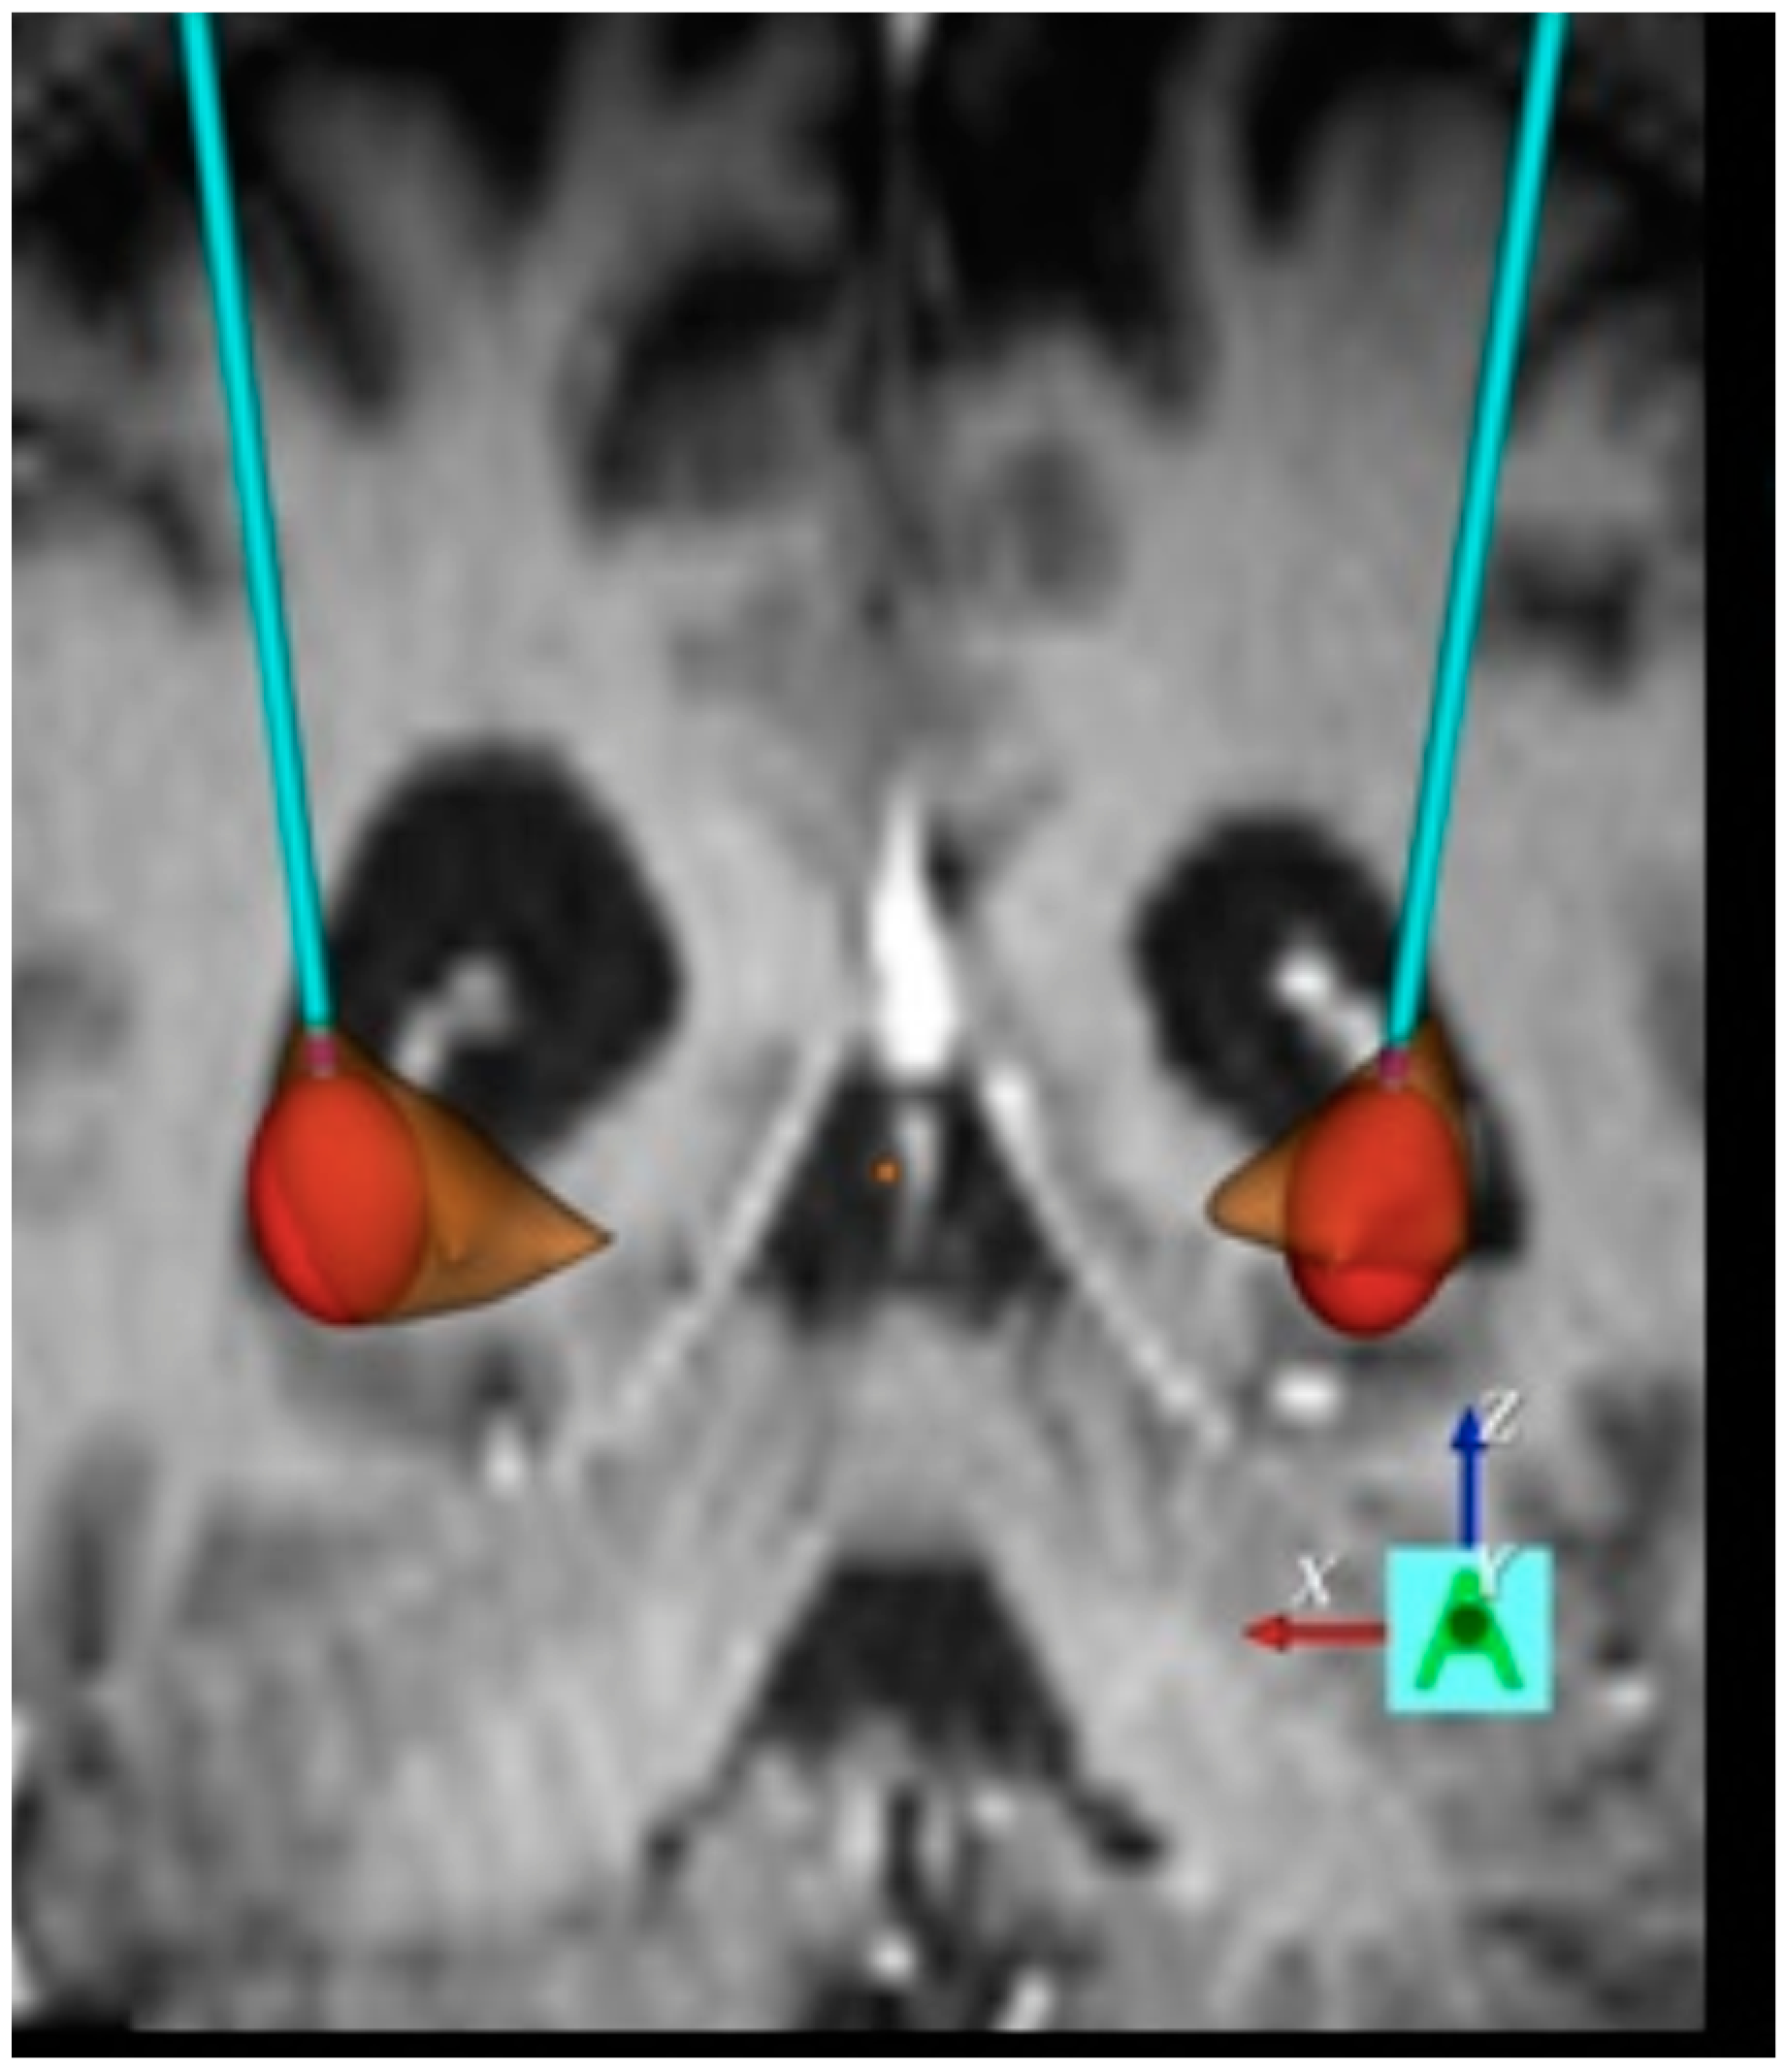

3. Invasive Assessment of the Basal Ganglia Network in HD

4. Clinical Implications of DBS in HD

4.1. Clinical Implications of DBS on Hyperkinetic and Hypokinetic Symptoms